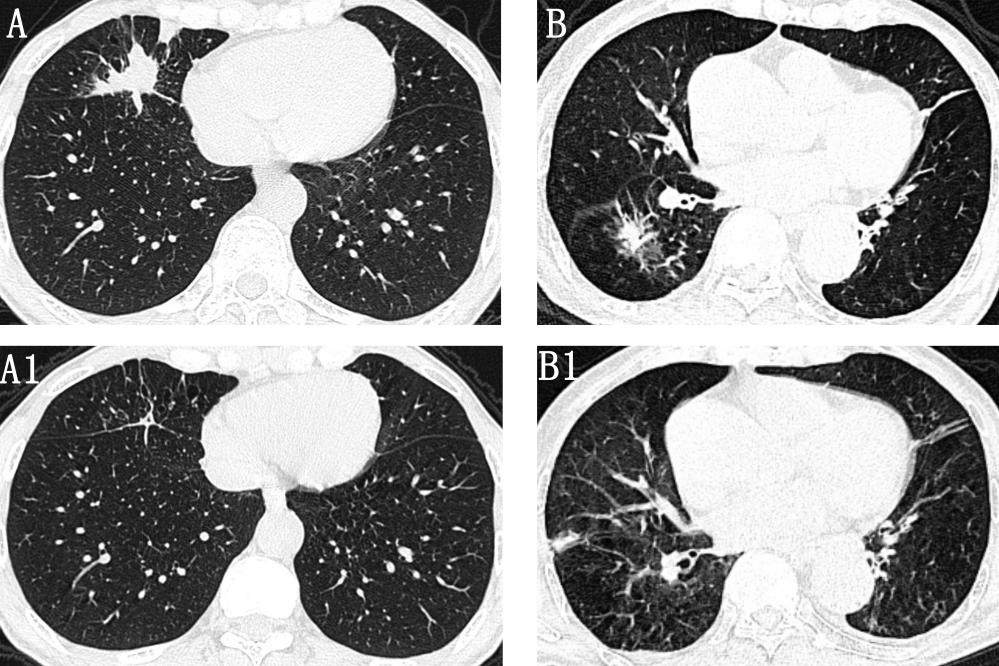

肿瘤型COPD-IPA的胸部CT表现

图像来自两位男性COPD-IPA患者(年龄分别为57岁和73岁),CT显示孤立性肺结节,边缘带毛刺,密度不均(A、B)。抗真菌治疗后复查CT显示两位患者的肺部病变均明显改善(A1、B1)。